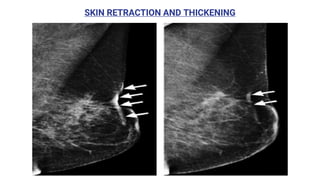

SKIN RETRACTION AND THICKENING

• #27 Moderate post-APBI focal skin thickening. (a) Mediolateral oblique mammogram of the left breast demonstrates moderate skin thickening (3-5 mm) (arrows), along with skin retraction. (b) Follow-up mediolateral oblique mammogram obtained 1 year later demonstrates regression of the skin thickening (arrows), which is now mild (<3 mm), as well as skin retraction. Note the maturation of the scar, with an interval decrease in regional density and contracture of the scar.